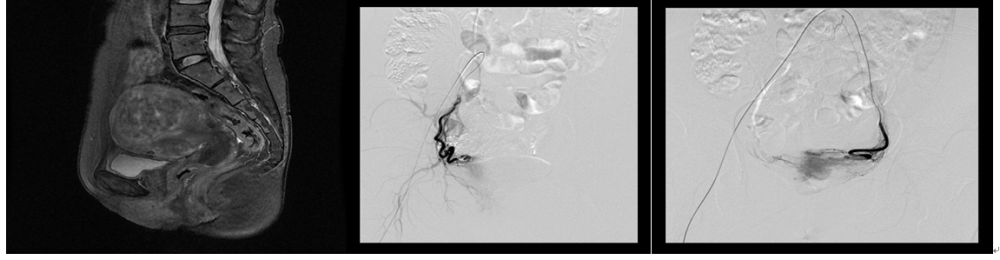

案例6:王**,女,41岁,经期延长、经量增多1年半,血红蛋白(Hb)72g/l,MRI提示多发子宫肌瘤,子宫大小约11.7*9.7*10.2cm,基本排除恶变可能,患者要求介入治疗,行双侧子宫动脉栓塞术,术后5月复查:症状完全缓解,Hb116g/l。